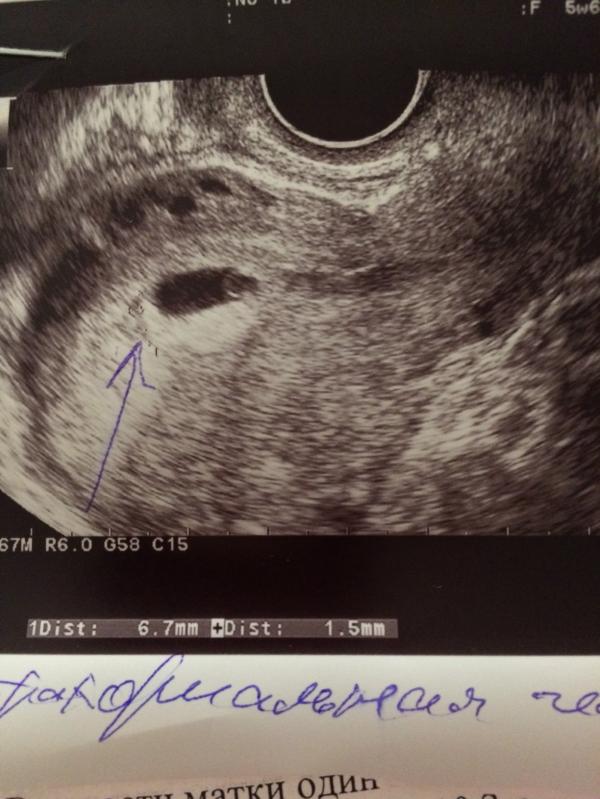

Ретрохориальная гематома!

Девочки, у кого как было?! Расскажите!!! Диагноз по УЗИ Ретрохориальная гематома на сроке 5 недель. Пролечилась. Выделения прекратились. На скоре 8 недель на УЗИ гематомы нет, но снова появились выделения. Беспокоюсь!!!